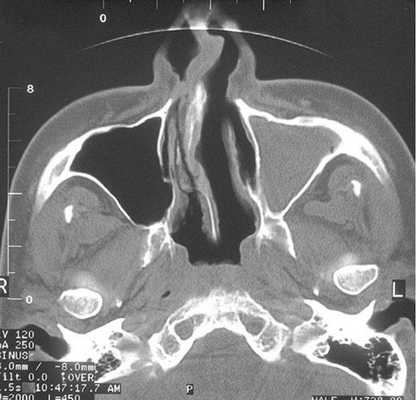

Тотальное заполнение жидкостью (кровью?) левой верхнечелюстной пазухи, повреждение носовой перегородки на компьютерной томограмме